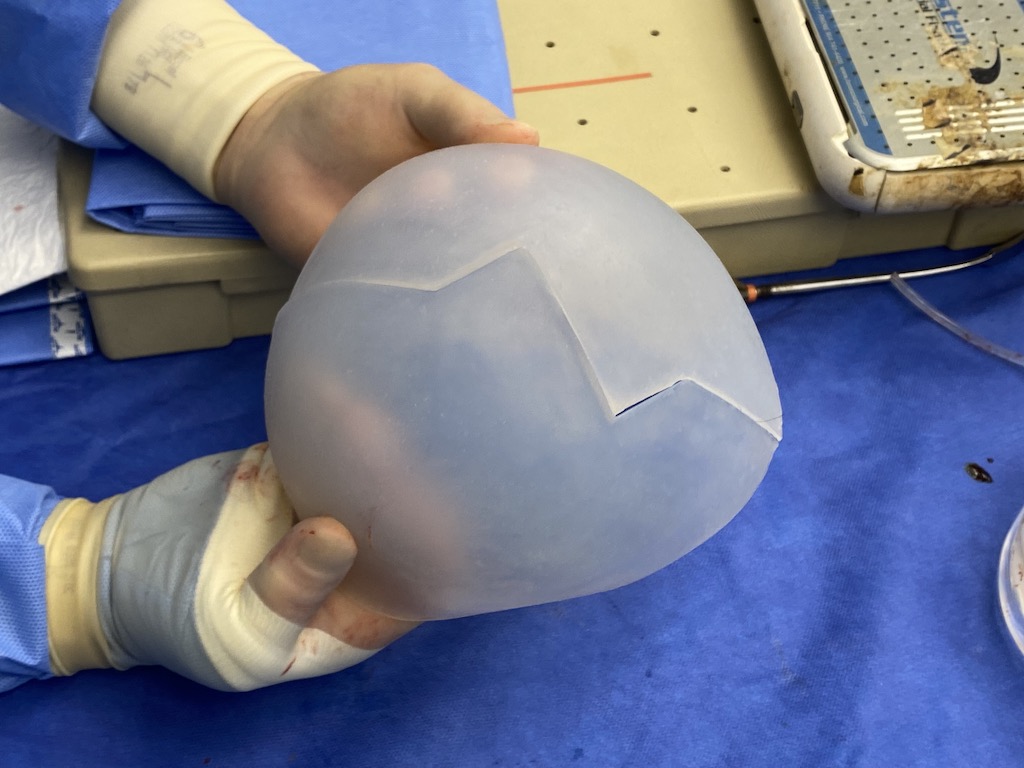

Desire for major head reshaping with a taler and wider head shape.

Placement of large two piece custom skull implant through a sagittal scalp incision.

Desire for major head reshaping with a taler and wider head shape.

Placement of large two piece custom skull implant through a sagittal scalp incision.